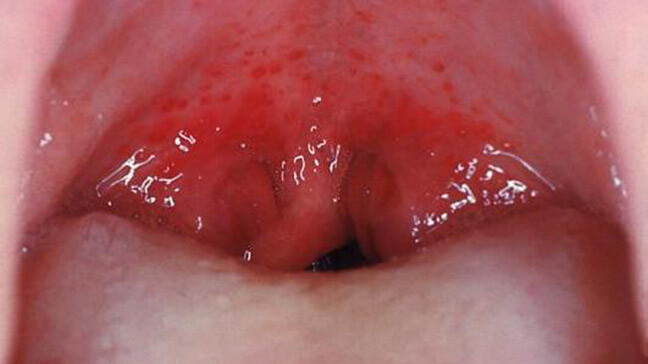

Gingivitis/ Gum DiseaseGingivitis is a first stage of gum disease and needs and needs early intervention or it can progress further into bone loss and eventually loss of teeth. The symptoms of gum disease include red and swollen gums that bleed easily.

Care – Follow your routine teeth care and visit your dentists regularly for oral check-up and cleaning.

EXAMINING YOUR GUMS

Your dentist always checks the health of your gums during a dental exam. They'll be looking for any signs of bleeding, swelling, or large gum pockets, all of which are signs of potential gum disease.